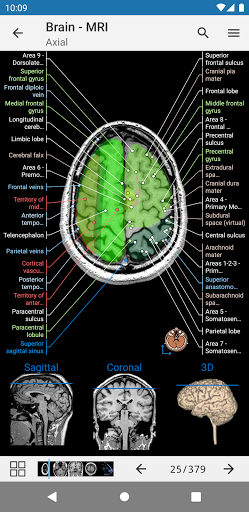

e-Anatomy memiliki lebih dari 26.000 gambar yang berisi serangkaian gambar dalam tampilan aksial, koronal, dan sagital serta radiografi, angiografi, gambar diseksi, bagan anatomi, dan ilustrasi. Semua gambar medis diberi label dengan cermat, lebih dari 967.000 label tersedia dalam 12 bahasa termasuk Terminologia Anatomica Latin.

- Gulir set gambar dengan menyeret jari Anda

- Perbesar dan perkecil

- Ketuk label untuk menampilkan struktur anatomi